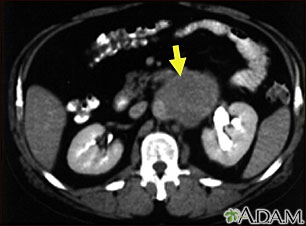

A CT scan of the middle abdomen showing a large tumor mass due to metastasis (spreading cancer) in abdominal lymph nodes.